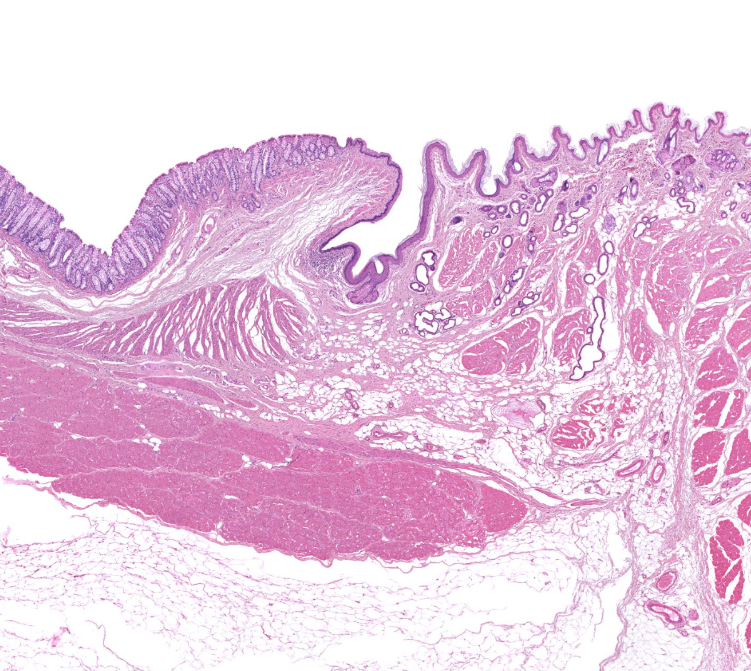

gastroesophageal junction

notice the shift from strat squamous to simple columnar (with long linear/coiled glands)

esophagus

note strat sq. epi

mucosa of esophagus

strat.squamous n-keratineized epi